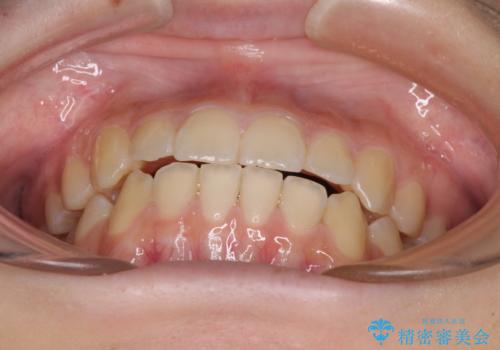

前歯のクロスバイト メタル装置での矯正治療

- 前歯のクロスバイトを気にして来院された患者様です。

前歯の叢生を解消するスペースを獲得するために上顎左右の親知らずを抜歯し、メタルブラケットにて矯正治療を行うこととしました。